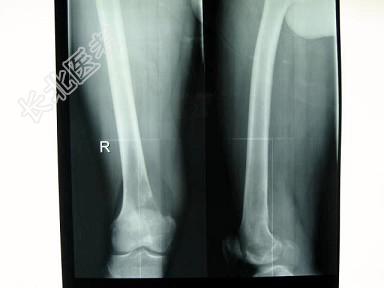

- 单项选择题男性患者,29岁, 右侧下肢疼痛3个月,行X线片及骨显像检查, 正确的诊断是 ( )

A、右侧股骨下端溶骨性骨肉瘤

B、右侧下肢膝关节炎

C、右侧股骨下端骨纤维肉瘤

D、右侧股骨下端成骨性骨肉瘤

E、以上都不是